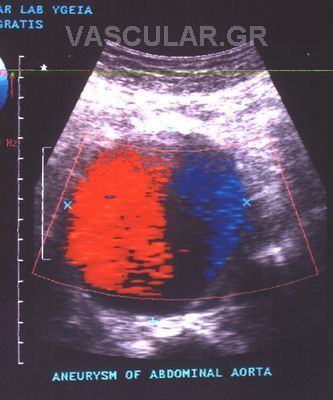

Ôï áíåýñõóìá ôçò êïéëéáêÞò áïñôÞò åßíáé ç ðéï êïéíÞ ðáèïëïãéêÞ êáôÜóôáóç êáé áíåõñßóêåôáé óôï 2-3% ôùí áôüìùí. Ç áñôçñéïóêëÞñõíóç åßíáé ç ðéï óõ÷íÞ áéôßá , ÷ùñßò íá áðïêëåßïíôáé ïé Üëëïé áéôéïãüíïé ðáñÜãïíôåò, üðùò åßíáé ôï ôñáýìá, ç ìüëõíóç ê.ë.ð. Ôï 98% ôùí êïéëéáêþí áíåõñõóìÜôùí åßíáé óáêïåéäÞ Þ åëéêïåéäÞ êÜôù áðï ôéò íåöñéêÝò.

Ç ðéóôüôçôá ôçò åîåôÜóåùò ìå ôïõò õðåñÞ÷ïõò êáôÜ ôç äéåèíÞ âéâëéïãñáößá êáé áðü ôç äéêÞ ìáò åìðåéñßá áíÝñ÷åôáé óôï 100% êáé ïé ìåëÝôåò Ýäåéîáí üôé ç áïñôÞ ìðïñåß íá ìåôñçèåß ìå áêñßâåéá 2 ÷éëéïóôÜ, óõãêñéíüìåíá ìå ôá ÷åéñïõñãéêÜ åõñÞìáôá.

Ìåñéêïß óõããñáöåßò áíáöÝñïõí, üôé ãéá êïéëéáêÜ áíåõñýóìáôá 3-6cm ï ìÝóïò üñïò áõîÞóåùò ôçò äéáìÝôñïõ ôïõ áíåõñýóìáôïò åßíáé 0,4cm êáô Ýôïò, åíþ ãéá áíåõñýóìáôá ìåãÝèïõò Üíù ôùí 6cm ï ìÝóïò üñïò áõîÞóåùò åßíáé 0,64cm êáô Ýôïò.

ÑÞîç Áíåõñõóìáôïò êïéëéáêÞò áïñôÞò

Áíåýñõóìá ôçò êïéëéáêÞò áïñôÞò ôï ïðïßï Ý÷åé äéÜìåôñï ðÜíù áðü 7cm å÷åé 76% ðéèáíüôçôá íá ñáãåß åíôüò 5 åôþí, åíþ ôá áíåõñýóìáôá êÜôù ôùí 6cm äéáìÝôñïõ Ý÷ïõí 16% ðéèáíüôçôá ñÞîåùò êáôÜ ôçí äéÜñêåéá ôçò éäßáò ðåñéüäïõ. Áðü ôá áíåõñýóìáôá ìå 5cm äéÜìåôñï ìüíï ôï 5% ñÞãíõôáé êáôÜ ôç äéÜñêåéá ôùí 5 åôþí.